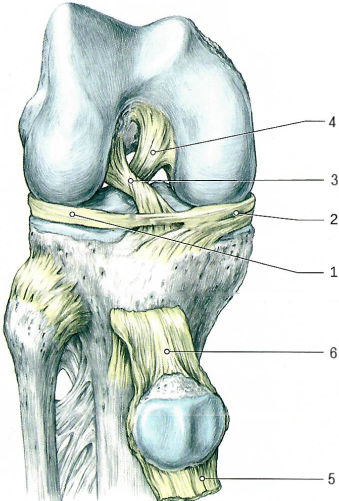

Коленный сустав по строению сложный, комплексный, по форме мыщелковый, по функции двуосный.

Сустав образован мыщелками и надколенниковой поверхностью бедра, верхней поверхностью большеберцовой кости, суставной поверхностью надколенника (имеет медиальный[2] и латеральный[1] мениски).

В суставе возможны сгибание и разгибание голени, вращение (при полусогнутом положении голени).

Связки, укрепляющие коленный сустав.